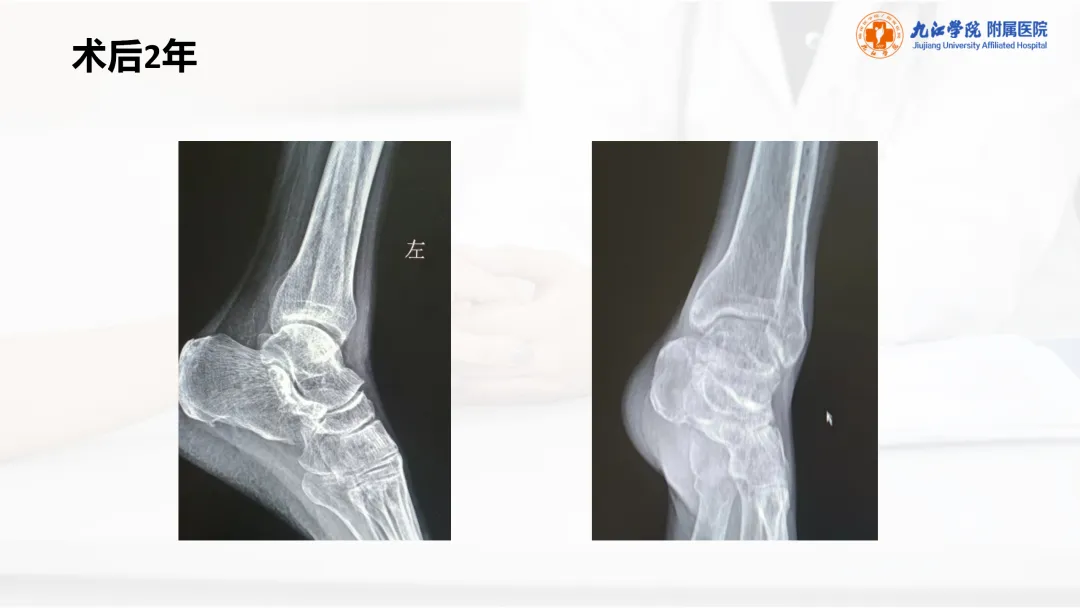

当前位置:首页>PPT>PPT纯享:陈旧性踝关节骨折的治疗案例(内附文献推荐)

PPT纯享:陈旧性踝关节骨折的治疗案例(内附文献推荐)